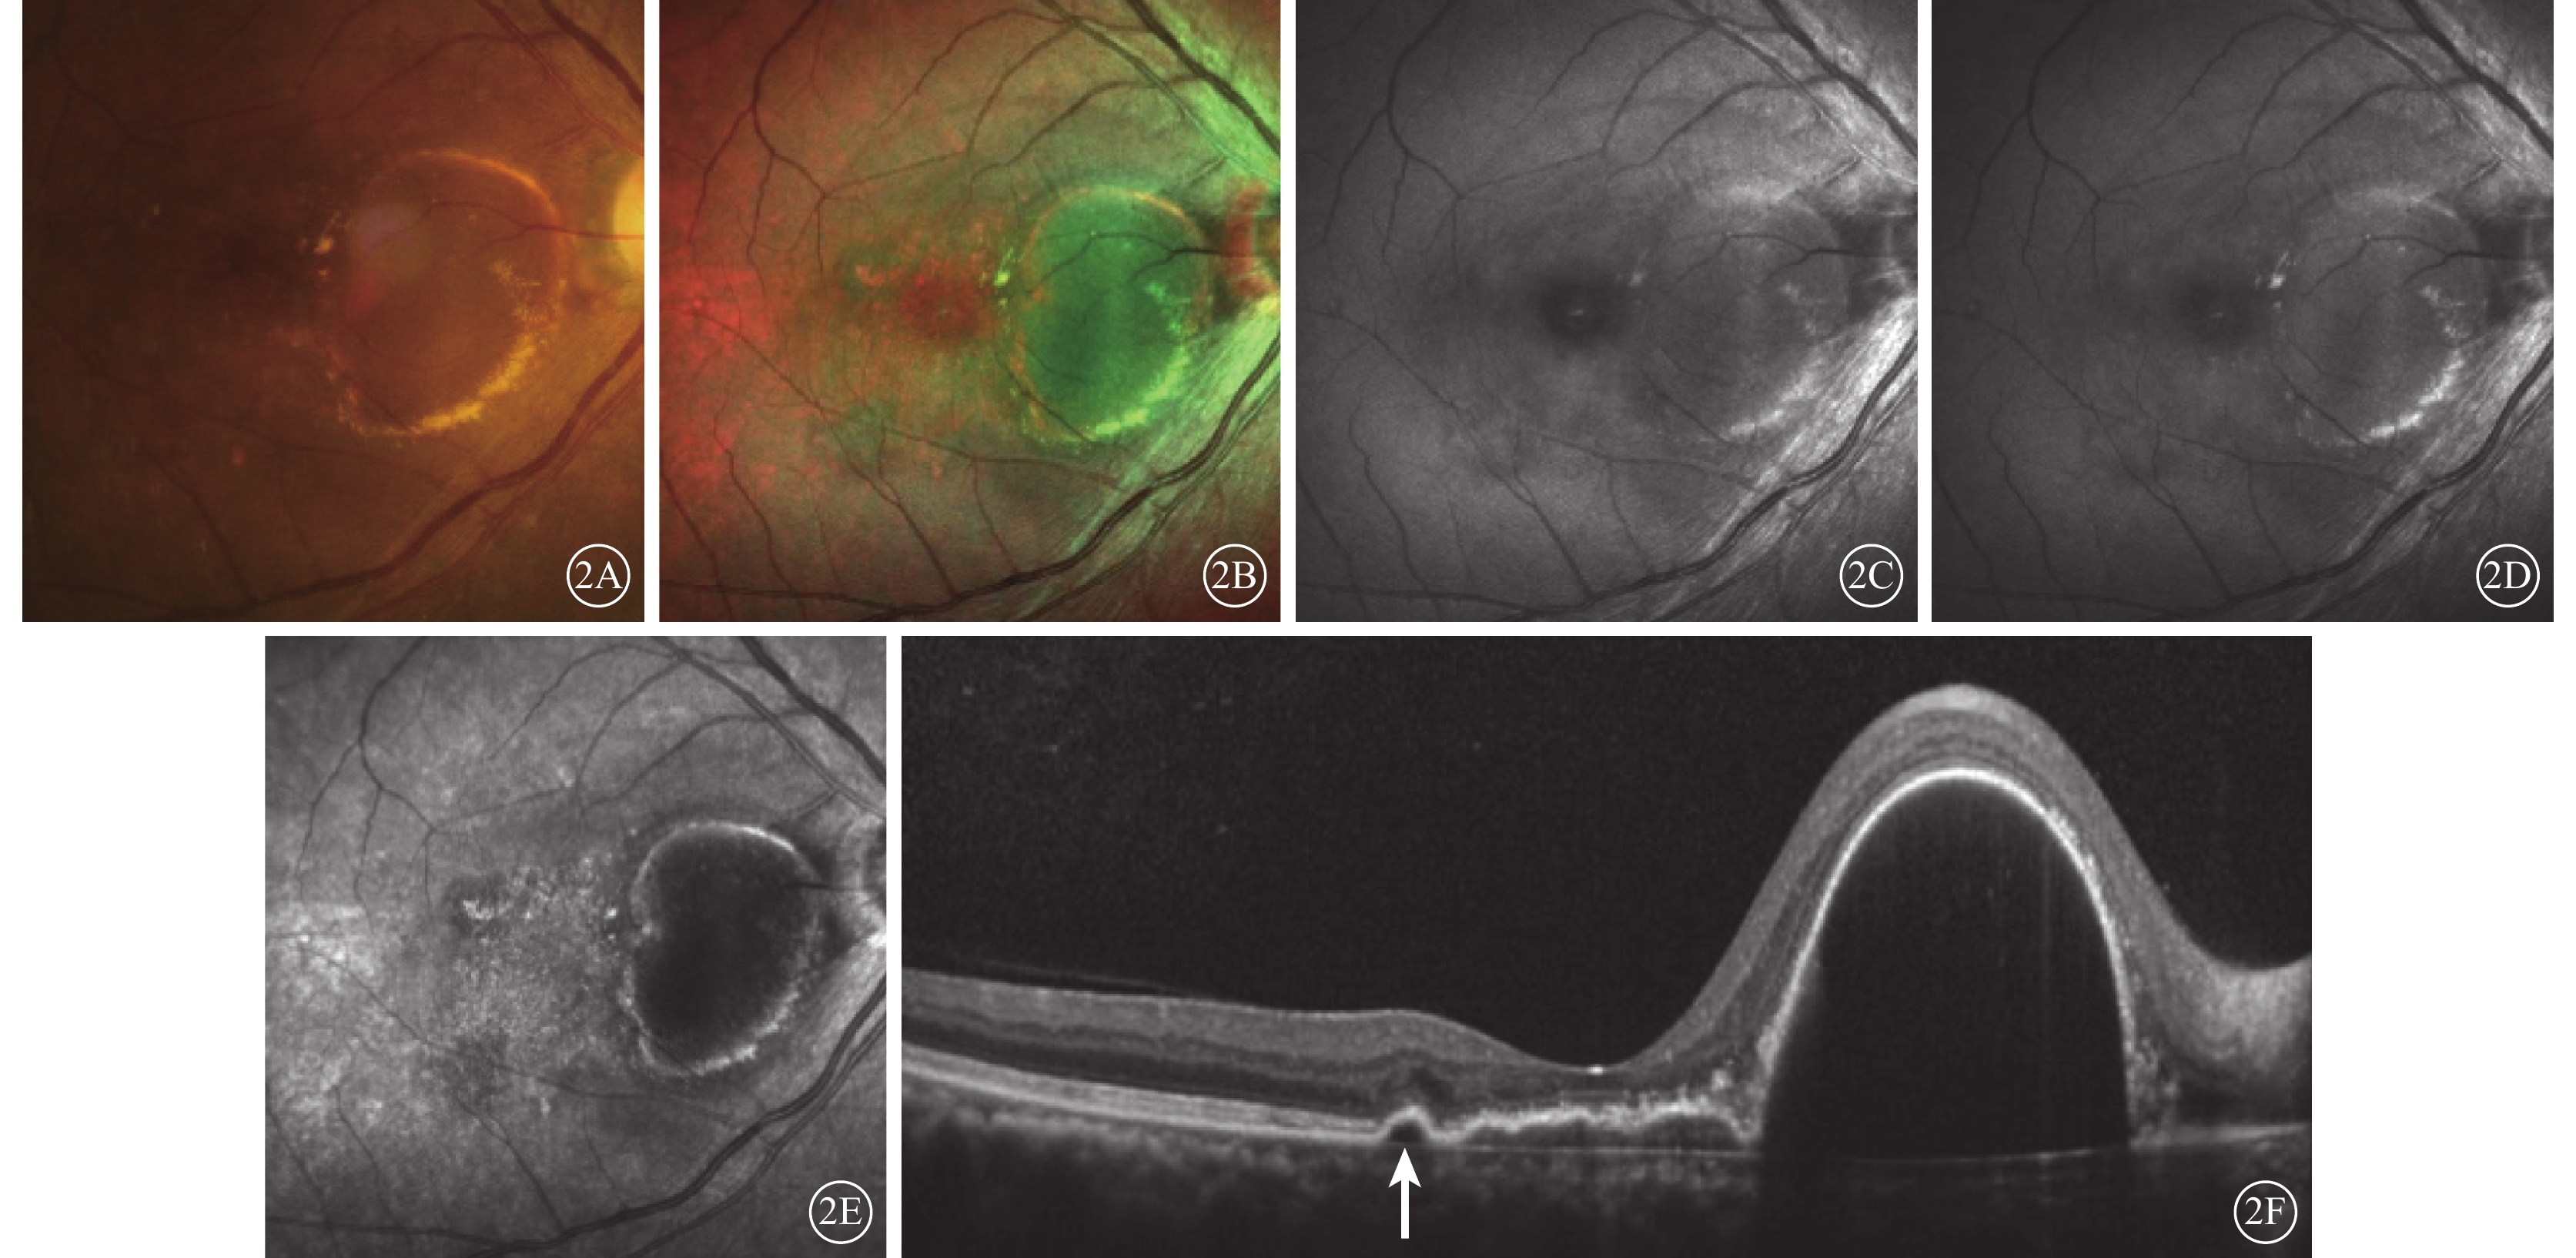

經多模式成像綜合判斷,32只眼中,漿液性PED(圖1)20只眼,出血性PED 3只眼,漿液性合并出血性PED 9只眼。

圖1

漿液性PED患眼FFA聯合ICGA像。1A示FFA像,可見黃斑下方局部有滲漏;1B示ICGA像,可見黃斑下方脈絡膜異常血管網

圖1

漿液性PED患眼FFA聯合ICGA像。1A示FFA像,可見黃斑下方局部有滲漏;1B示ICGA像,可見黃斑下方脈絡膜異常血管網

經多模式成像綜合判斷,32只眼中,漿液性PED(圖1)20只眼,出血性PED 3只眼,漿液性合并出血性PED 9只眼。

圖1

漿液性PED患眼FFA聯合ICGA像。1A示FFA像,可見黃斑下方局部有滲漏;1B示ICGA像,可見黃斑下方脈絡膜異常血管網

圖1

漿液性PED患眼FFA聯合ICGA像。1A示FFA像,可見黃斑下方局部有滲漏;1B示ICGA像,可見黃斑下方脈絡膜異常血管網